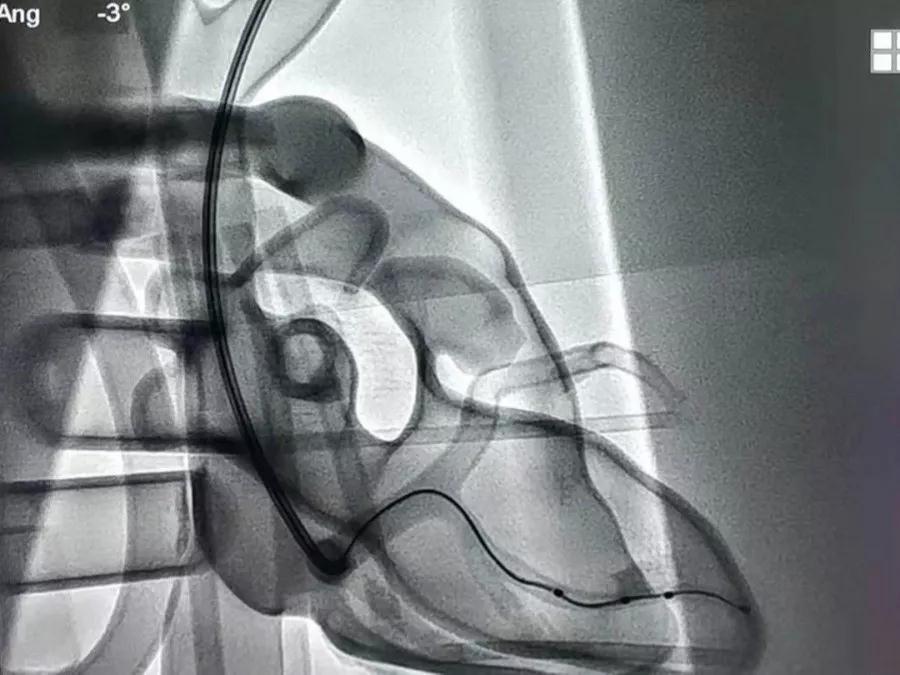

术者在X影像下将Quartet™ 1458Q左室四极电极成功植入于雅培“心动”模型的侧静脉。

基于此,雅培公司CRM部门外部培训团队于2019年7月自主设计推出了国内乃至全球首个专用于起搏导线植入及左室导线植入的3D 心脏介入手术全真模拟系统-“心动”模型。临床医生可在模型上,全真模拟起搏器或CRT手术植入流程,感受到与真实心腔以及静脉血流下相同的操作手感,同时该模型在X影像下可以呈现出完整的心脏结构。

2019年7月29日,“心动”模型于雅培起搏之路-大连站首次亮相。当日,7名术者在C臂的真实X影像下进行了起搏手术和CRT手术的全真手术模拟,当心房电极到位时,术者惊喜的发现心房电极在心脏模型的右心耳出现了与真实病人相同的一点钟方向左右摆动,“心动”模型取得了圆满成功。